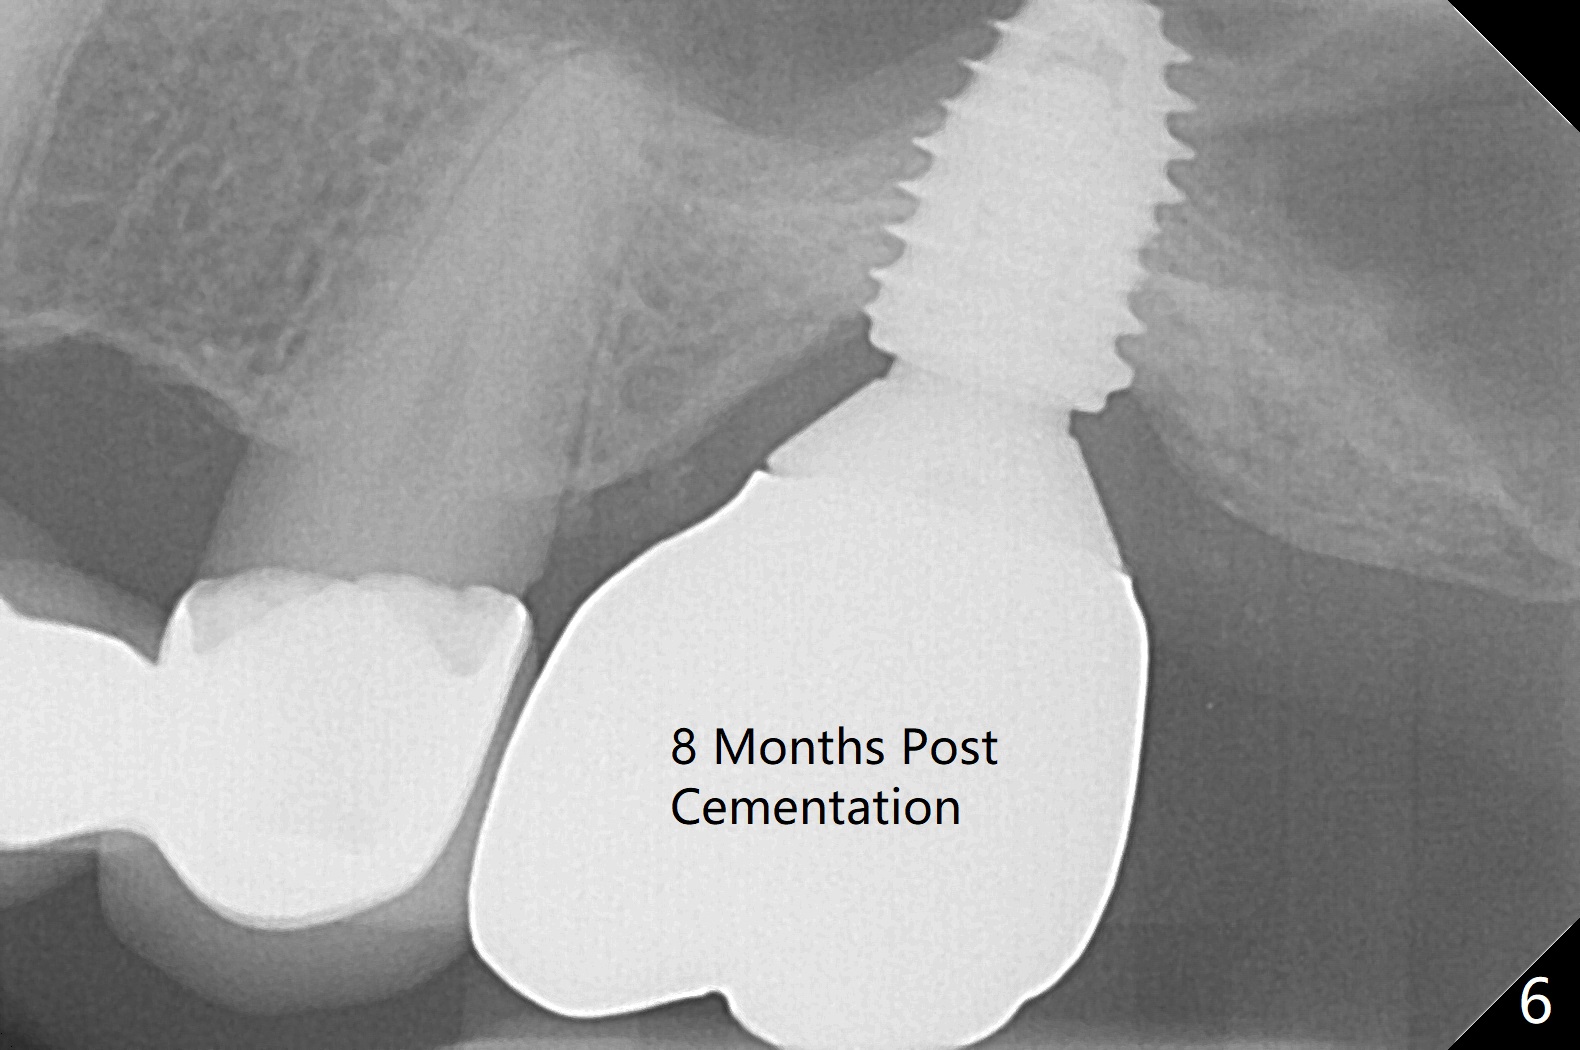

When the non-osteointegrated implant is removed, the sinus membrane is found to have been perforated. There is a history of clear discharge immediately postop ~ 1 year ago. Against the common wisdom, a 5x10 mm dummy implant is inserted with intention to correct the trajectory and 50 Ncm (Fig.1). With placement of Osteogen plug (presumably for repair of the perforation) and limited amount of Vanilla at the osteotomy, a 5x7.3 mm IS implant with SLA surface treatment is placed (Fig.2, ~ 40 Ncm). When the implant is further seated (Fig.3 arrow with bone graft coronally *)), its trajectory is within the normal limit (Fig.4 blue line). If the implant fails again, it must be due to the mild sinus infection. Bone graft, or preferably Osteogen Plug (collagen with osteoconductive ability) should have been done first. Mild tenderness exists with use of Water Pik 7 months post 2nd placement (Fig.5). Uncover shows that the implant is stable. A 6x3 mm healing abutment is placed. Next appointment a temporary crown will be fabricated for progressive loading. The abutment screw needs retightening 8 months post cementation, probably related to poor crown/implant ratio and missing 2nd molar (Fig.6).